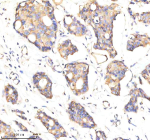

Immunohistochemical staining of GBF1 using anti-GBF1 antibody. GBF1 was detected in a paraffin-embedded section of human prostate cancer tissue. Heat mediated antigen retrieval was performed in EDTA buffer (pH 8.0, epitope retrieval solution). The tissue section was blocked with 10% goat serum. The tissue section was then incubated with 2 ug/ml rabbit anti-GBF1 antibody overnight at 4oC. Peroxidase Conjugated Goat Anti-rabbit IgG was used as secondary antibody and incubated for 30 minutes at 37oC. The tissue section was developed using an HRP secondary and DAB substrate.